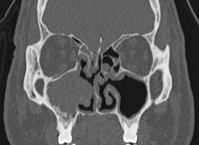

A 52year old male of Samoan descent presented to our centre in year 2003 with long term (>10years) nasal obstruction and clear nasal discharge. Anterior rhinoscopy showed bilateral grade IV nasal polyps. Nasoendoscopic examination of the left nasal cavity revealed numerous pale polypoid masses in the inferior meatus and middle meatus whilst the right nasal cavity was completely full of polyps. Computerized tomography (CT) scan revealed extensive bilateral disease with polyposis involving the paranasal sinuses, nasal cavity and nasopharynx. There was no evidence of bony sclerosis, thickening or destruction (Figure 1). He suffered from asthma and had undergone bilateral functional endoscopic sinus surgery (FESS) previously elsewhere. In 2004, with a preoperative diagnosis of chronic rhinosinusitis with bilateral polyposis, a revision FESS was preformed and the polyps were sent for histological examination. On macroscopic examination, the polyps from both sides appeared smooth, shiny and cream in colour. Histological examination of polypoid fragments from both sides was consistent with bilateral synchronous Shneiderian papilloma along with inflammatory polyposis.

Figure 1 Bilateral mucoperiosteal disease worse affecting the right nasal cavity (Year 2004).